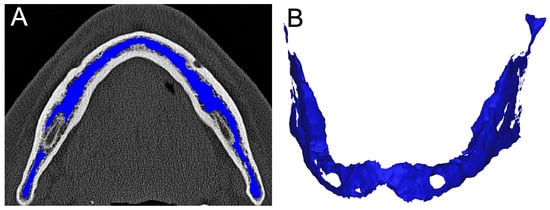

2.4. Image Analysis and Segmentation

2.6. Segmentation